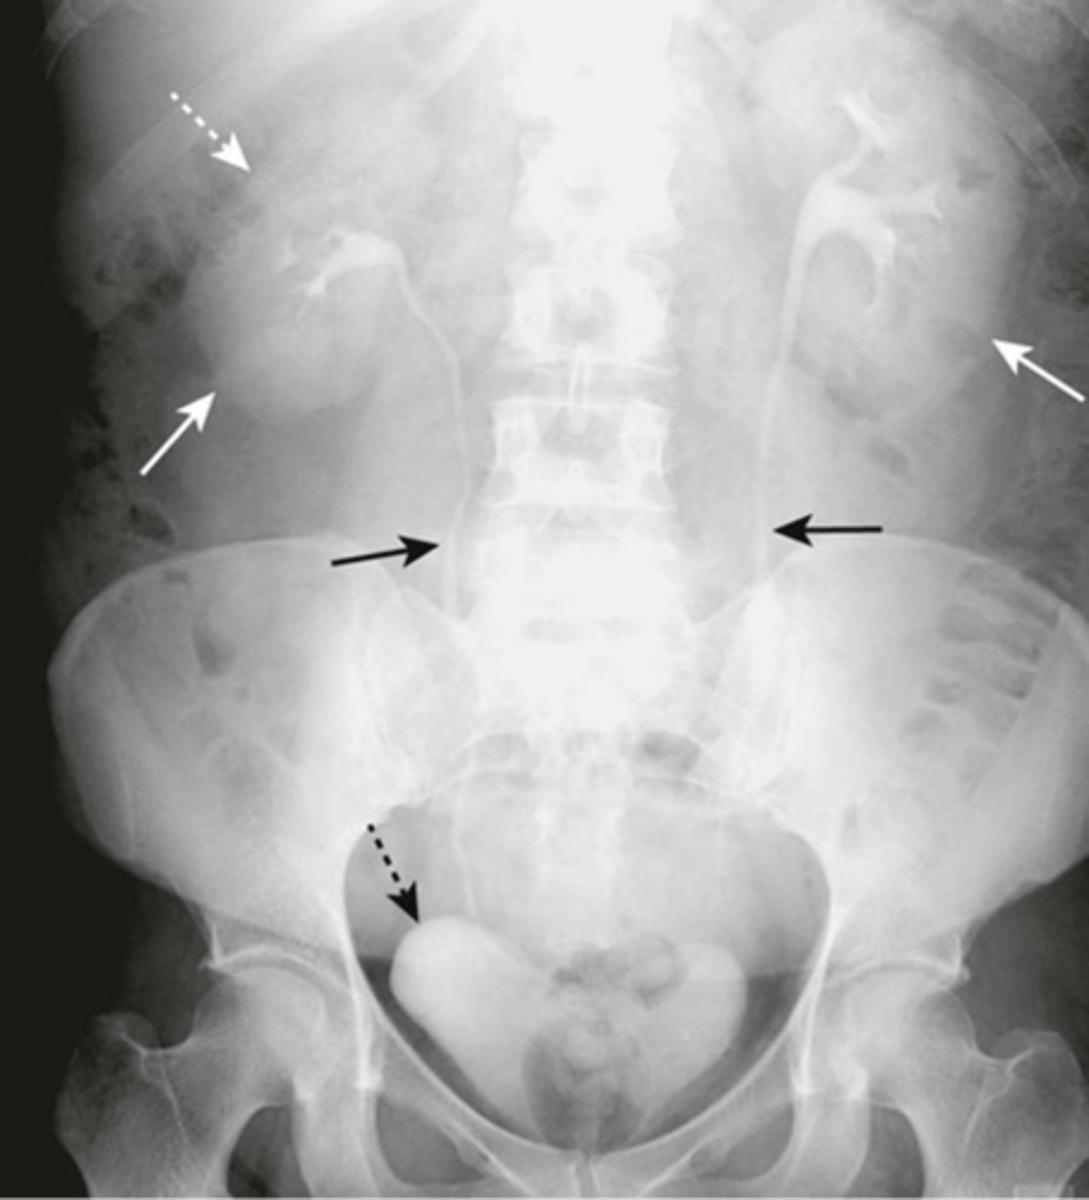

Normal bladder

left: distended bladder

right: enlarged uterus